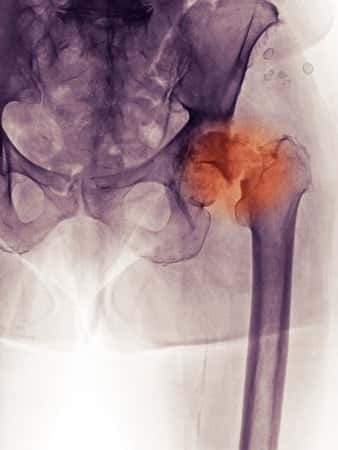

This case involves a fifty-six-year-old male who underwent a right total hip arthroplasty. The patient subsequently leached cobalt out of the Stryker Trident ceramic replacement device, causing toxic levels to enter the bloodstream. The resultant cobalt poisoning lead to the following complications: fatigue, insomnia, irregular thyroid function, hip pain, peripheral neuropathy and numbness, hair loss, skin discoloration, rash, blotching, broken and cracked teeth, weakened gums, sexual dysfunction, infection (debris), tumor (interior to hip), tumor (on hand), aggravation of asthma, eyes (miosis, vision disturbance, dryness), chest pain, headache, urinary problems, multi-organ failure, and irregular bowel movements. The serum cobalt levels continue to be high in the patient despite medical management, and the patient’s severe dental complications in particular have dramatically decreased his standard of living; he has had to undergo numerous reconstructive surgeries, and now must wear special dentures with adhesives in order to accommodate his complications.

Though joint replacement devices have been safe for many years, companies are beginning to use new materials to engineer them differently. The primary issue with the metal-on-metal (MoM) are the small particles of chromium and cobalt that are released into the body from the hip replacement as the components on the hips begin to wear. These particles have already been shown to cause tissue damage and can develop into what are being termed “pseudotumors” at the site of the hip replacement. These particles then make their way into the blood stream and cause heavy metal poisoning in the recipients of MoM hip replacements. Both chromium and cobalt can be toxic in the human body at certain levels. There have already been patients with MoM hip replacements that have been diagnosed with heavy metal poisoning. Some of the possible side effects from toxic levels of chromium or cobalt are cancer, renal tubular damage, liver and kidney problems including failure, cardiovascular collapse and failure, visual impairment including blindness, auditory problems including deafness, neurological damage, and death. The main problem is it takes time for the device to deteriorate and release these particles into the blood stream. Hence, the companies had already allowed thousands of these devices to be implanted before the toxicities appeared.